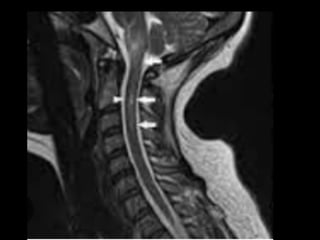

• SINAL  DE  LHERMITTE:  sensação  de  choque   elétrico  que  irradia  pelas  costas  e/ou  MMII   após  a  flexão  do  pescoço

critérios  McDonald  (2017)   • disseminação  no  espaço   – RM  por  ≥  1  lesões  hiperintensas  em  T2,   sintomá+cas  ou  assintomá+cas,  que  são   caracterís+cos  de  EM,  em  dois  ou  mais  das   seguintes  quatro  áreas  do  sistema  nervoso   central:     • periventricular,     • cor+cal/justacor+cal,  infratentorial  e  medula  espinhal.

• 45.